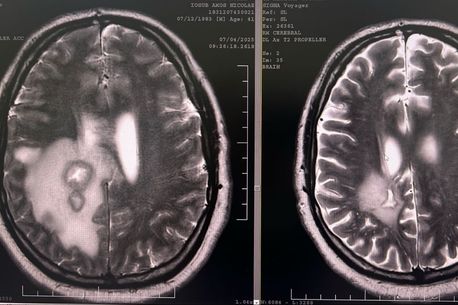

Iosub Amos Nicolae, canotor de performanță între anii 1998 și 2007 la clubul Steaua București, în prezent ofițer în cadrul Ministerului Apărării Naționale și tată a doi copii, în vârstă de 9 și 14 ani, a fost diagnosticat la începutul acestui an cu o formă galopantă de cancer la creier.

În luna ianuarie, medicii l-au diagnosticat pe Iosub Amos Nicolae cu glioblastom cerebral și de atunci fostul sportiv a trecut deja prin trei intervenții chirurgicale pe creier.

După ultima operație, specialiștii din București au transmis familiei că doar un vaccin ce poate fi produs în Germania îi poate prelungi viața lui Amos Nicolae. Iar medicamentul ce poate fi fabricat la o clinică specializată de cercetare costă 80.000 de euro.